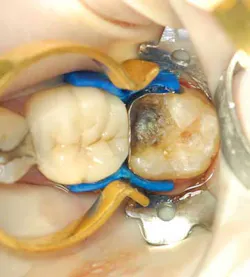

A 55-year-old male patient presented with a chief complaint of occasional hot and cold sensitivity involving his lower molar. Upon clinical examination, it was determined he had a failing amalgam and undermined mesial buccal cusp involving his second molar (Fig. 1). As per the Morgan and Presley’s prewedge protocol, a medium wedge was placed between the molars to initiate separation and protect the papilla. Upon removal of the old restoration and decay, it was decided to restore this tooth with a posterior composite material using the ABC Wedge. With a little imagination, this wedge looks like an elephant’s head and its parts will be described as such. The ears were designed to support the sectional band in three dimensions (3-D) and prevent the sectional rings from crushing in the matrix band (Fig. 2). The elephant’s trunk is analogous to the anatomic wedge. Two wedges were used from the buccal and lingual surfaces, and the curved trunks slide past each other to seal off the gingival floor (Fig. 3). A central groove is located on the back between the ears to line up the sectional separating ring and directs the pressure interproximally for maximum separation. The tooth was then easily restored in incremental layers, trimmed back, and the bite was adjusted (Fig. 4).